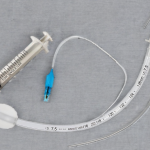

Benötigtest Material zur endotrachealen Intubation

Benötigtest Material zur endotrachealen Intubation

| Endotrachealtuben |

| Blockerspritze |

- Visuelle Kontrolle der Tubustiefe mittels der aufgedruckten Zentimeter-Skala

- Frauen meist 20-21 cm

- Männer meist 22-23 cm

- Endotrachealtubus Blocken

- 10ml Luft